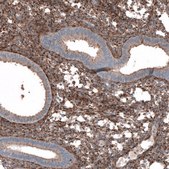

All Prestige Antibodies Powered by Atlas Antibodies are developed and validated by the Human Protein Atlas (HPA) project and as a result, are supported by the most extensive characterization in the industry.

The Human Protein Atlas project can be subdivided into three efforts: Human Tissue Atlas, Cancer Atlas, and Human Cell Atlas. The antibodies that have been generated in support of the Tissue and Cancer Atlas projects have been tested by immunohistochemistry against hundreds of normal and disease tissues and through the recent efforts of the Human Cell Atlas project, many have been characterized by immunofluorescence to map the human proteome not only at the tissue level but now at the subcellular level. These images and the collection of this vast data set can be viewed on the Human Protein Atlas (HPA) site by clicking on the Image Gallery link. We also provide Prestige Antibodies® protocols and other useful information.

• IHC tissue array of 44 normal human tissues and 20 of the most common cancer type tissues.